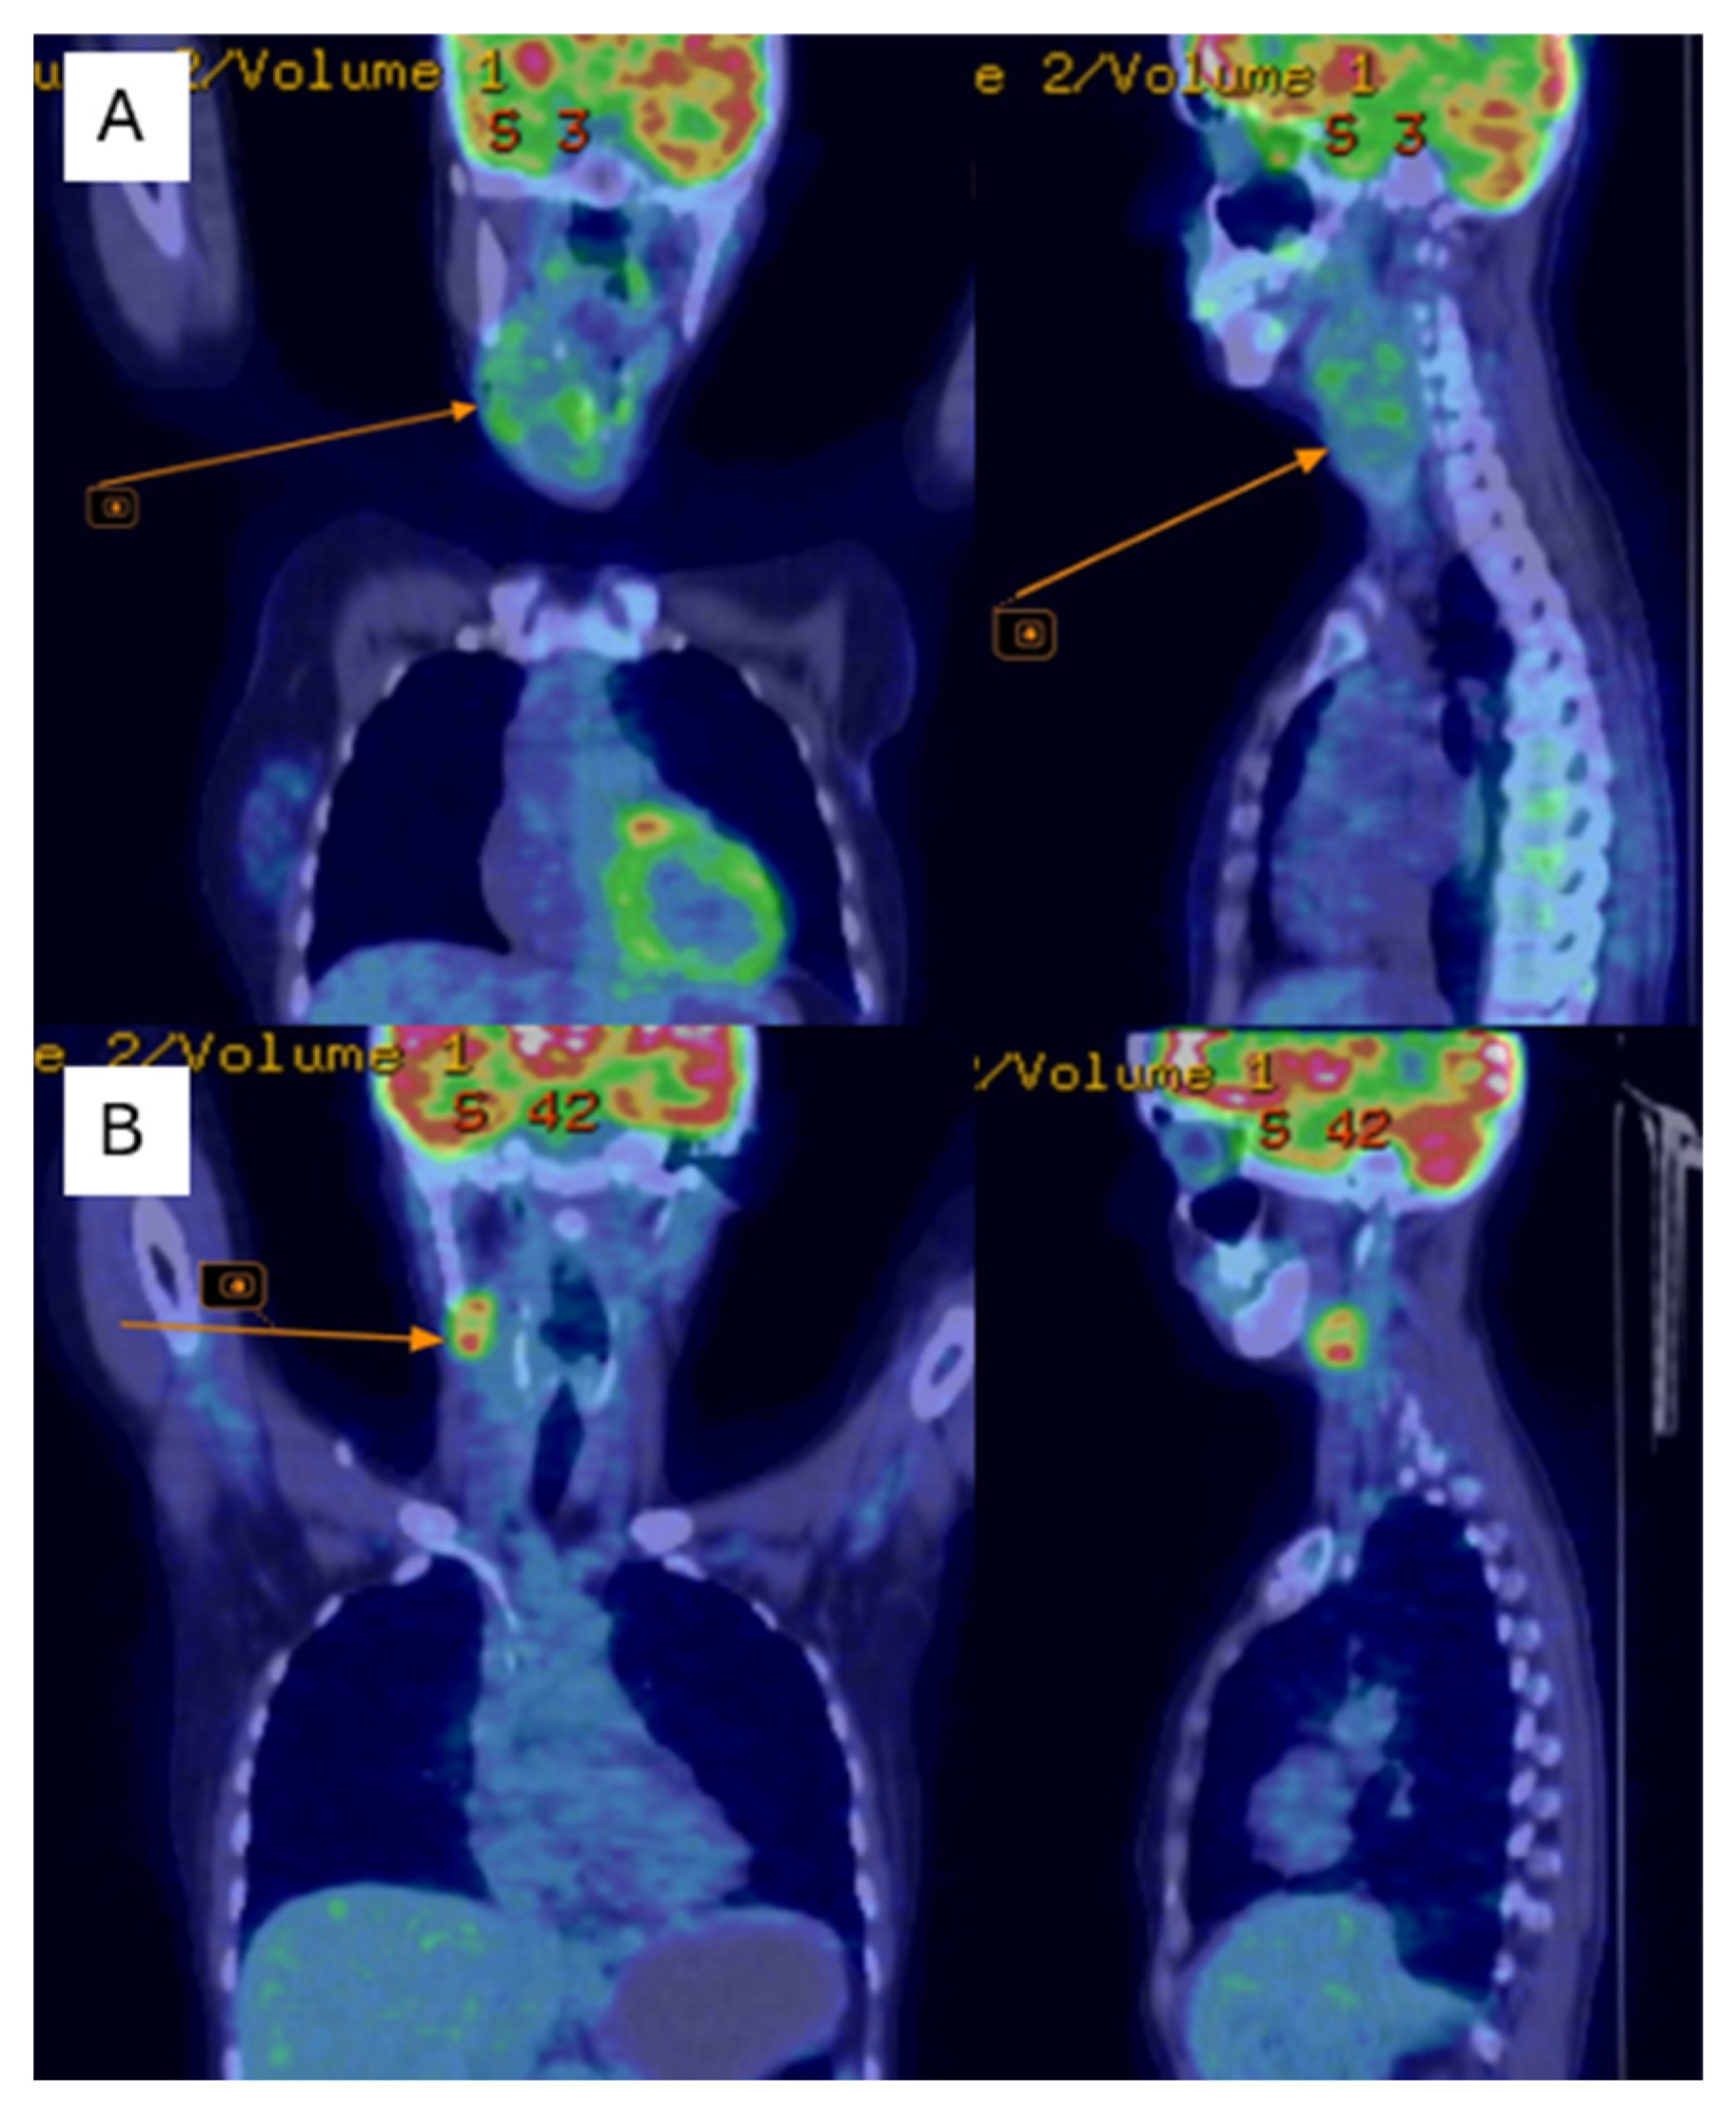

Postoperatively, the patient underwent adjuvant radiotherapy (total dose, 50 Gy in 25 fractions) to the left chest wall using a Halcyon linear accelerator, which was well-tolerated. Three months after radiotherapy, the patient developed dysphonia, and a subcutaneous tumor mass was observed in the right lateral cervical region. Cervical ultrasonography revealed immobile right lateral cervical lymphadenopathy measuring approximately 4 × 4 cm, with a normal-sized thyroid gland. Cervical magnetic resonance imaging (MRI) revealed a bilobed malignant tumor mass in the right laterocervical region, with invasion of the right thyroid cartilage and partial involvement of the right vocal cord. PET-CT showed metabolically active secondary lesions in the right lateral cervical lymph nodes and in the right lower pulmonary lobe (Figure 4A).

Figure 4.

PET-CT shows of the right jugular–carotid adenopathic mass (A)—before chemotherapy, (B)—after chemotherapy.

Follow-up cervical PET-CT (Figure 4B) and MRI (Figure 5A–C) showed a significant reduction in the size of the right jugular–carotid adenopathic mass, with residual lymphadenopathy and a favorable pulmonary response. No new metabolically active lesions were observed.